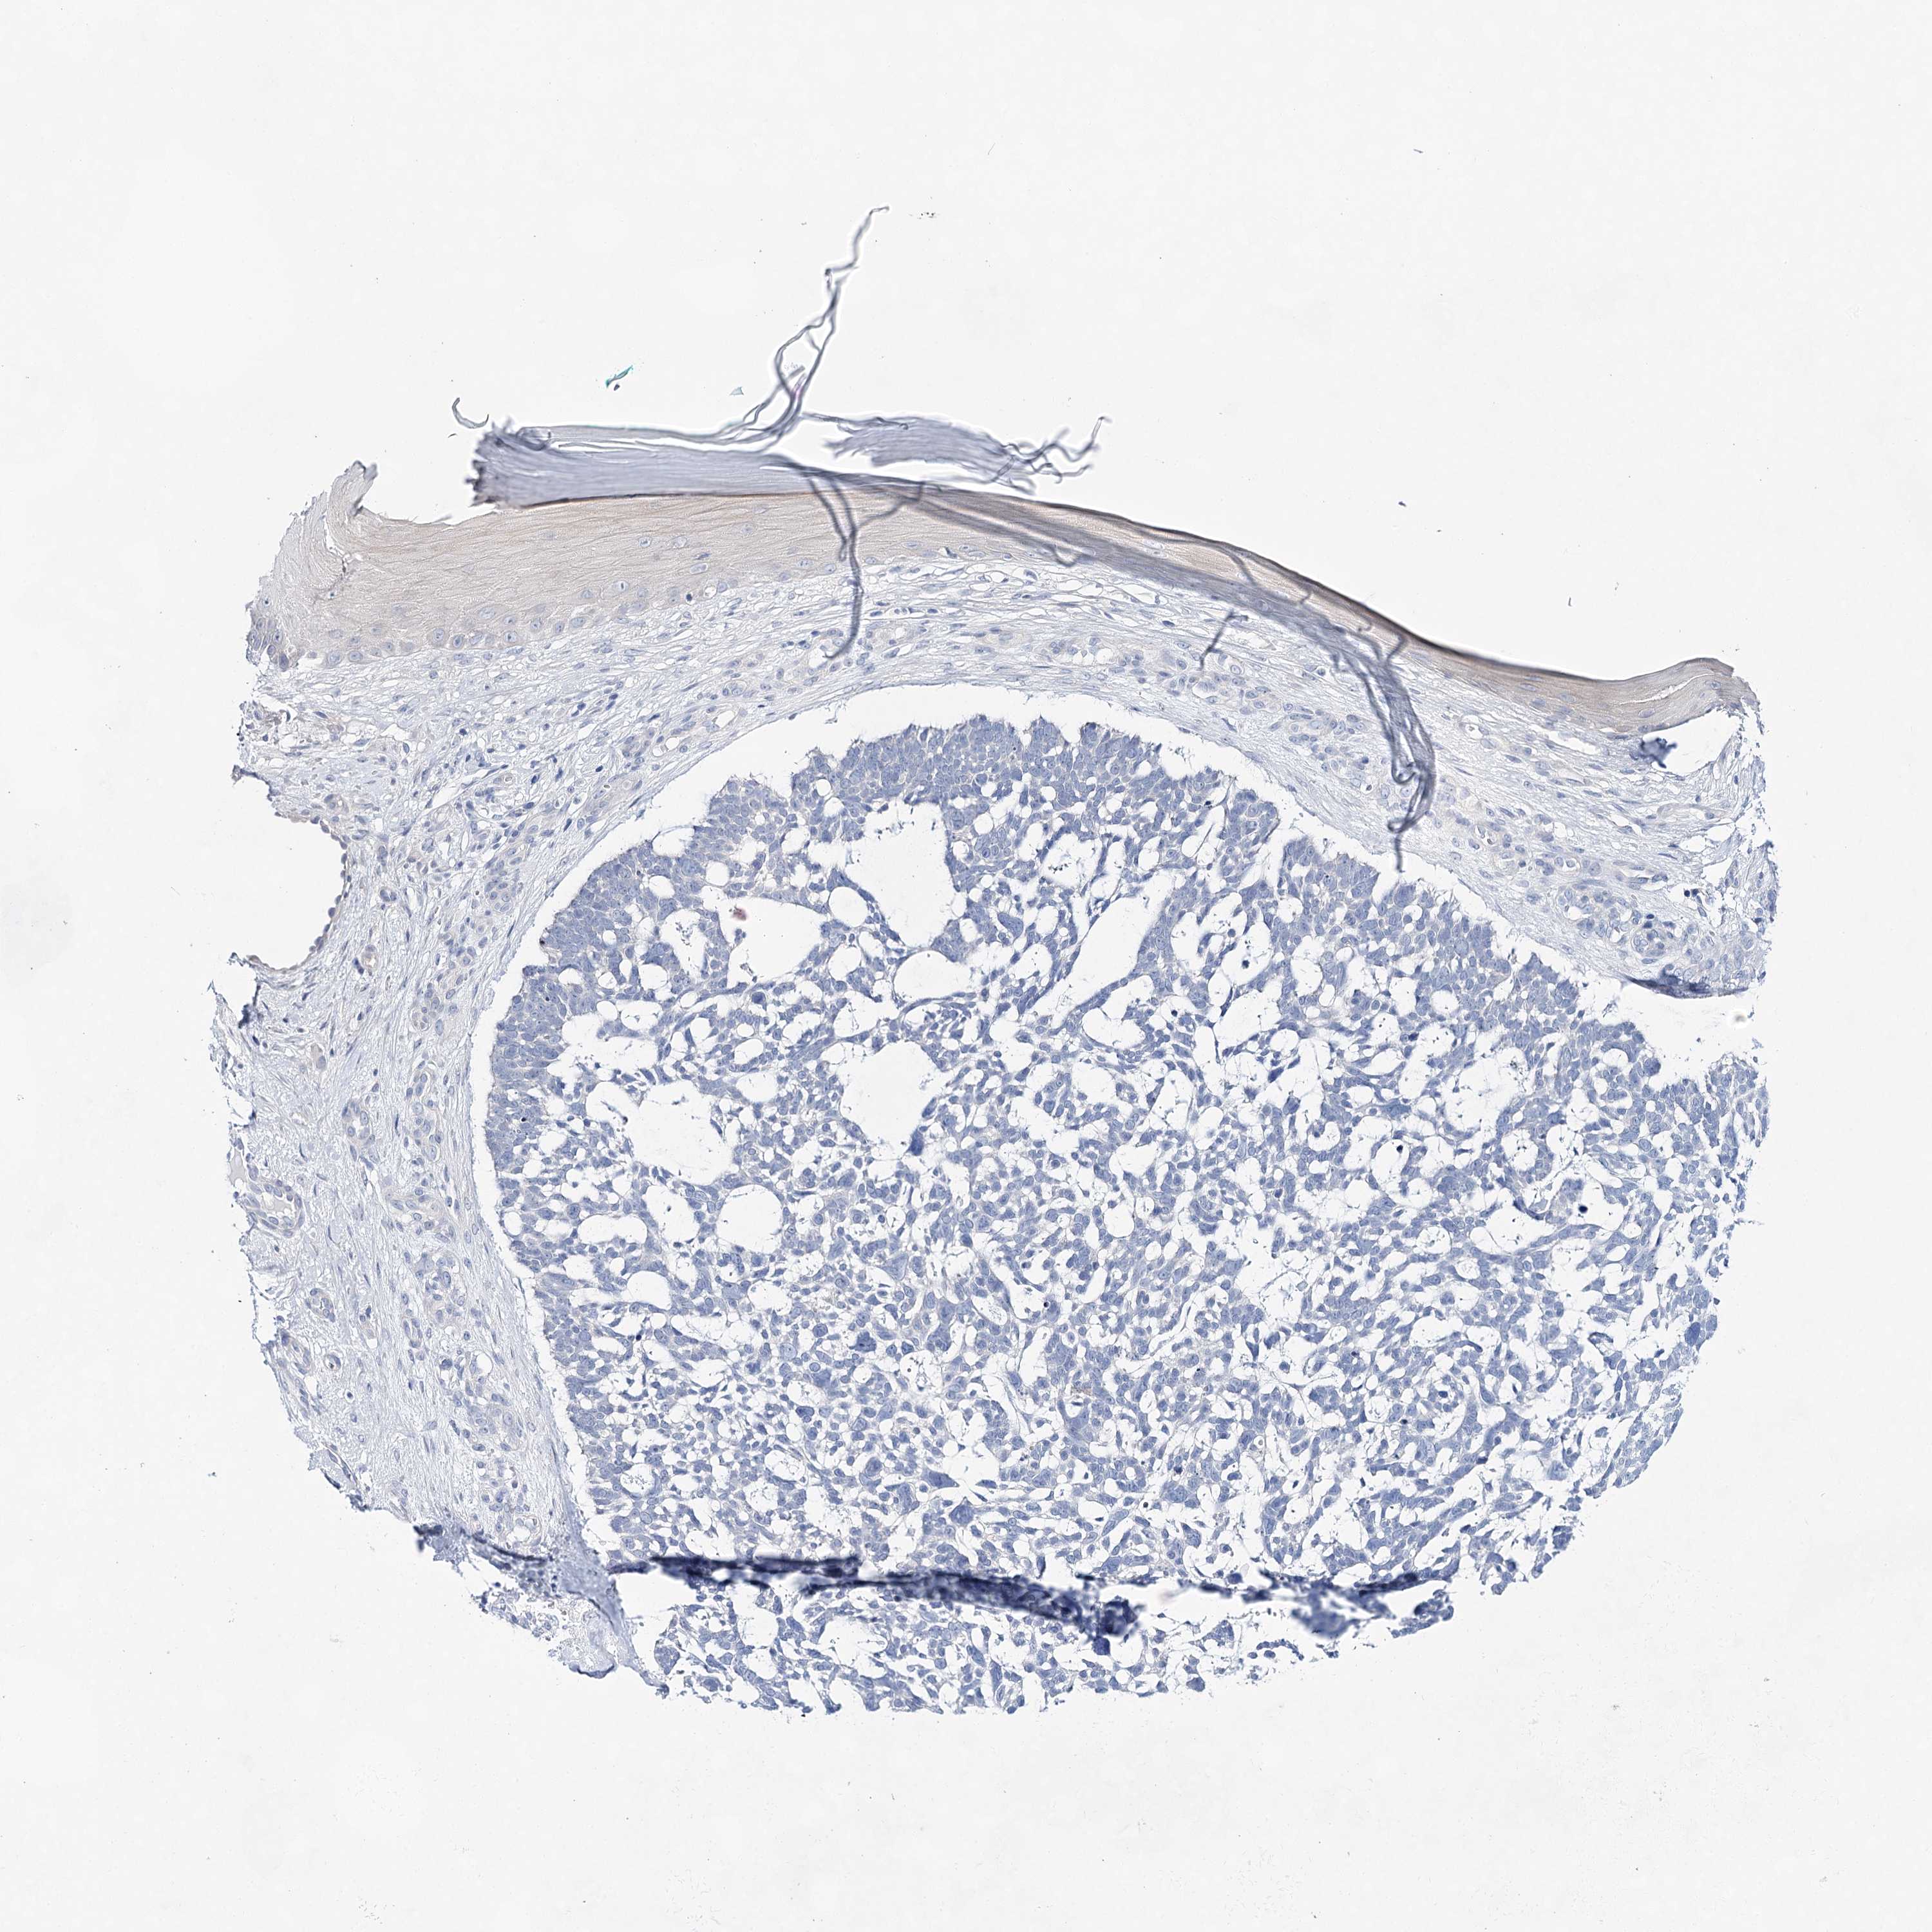

Basal cell and squamous cell cancer

SKIN CANCER - Protein expressioni

A mouse-over function shows sample information and annotation data. Click on an image to view it in a full screen mode. Samples can be filtered based on level of antibody staining by selecting one or several of the following categories: high, medium, low and not detected. The assay and annotation is described here.

Antibody staining in the annotated cell types in the current human tissue is reported as not detected, low, medium, or high, based on conventional immunohistochemistry profiling in selected tissues. This score is based on the combination of the staining intensity and fraction of stained cells.

Each image is clickable and will lead to virtual microscopy that enables deeper exploration of all samples and also displays staining intensity scores, fraction scores and subcellular localization as well as patient and tissue information for each sample.

Basal cell carcinoma